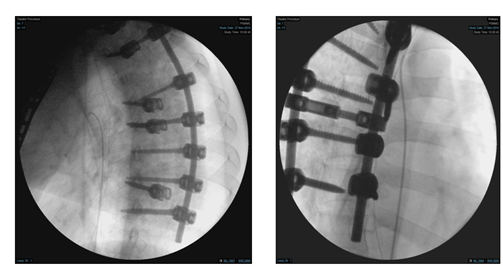

Figure 3 Anteroposterior (AP) & lateral views of left humerus, post open reduction and internal fixation by PHILOS plate (05.Sep .2019) [A&B ], with posterior spinal instrumentation from T1 -T7 [C].

On 27th of November 2019, patient underwent for removal of the pedicle screw under angiography which was a combined surgery between spine surgery and vascular surgery. Patient put in the lateral decubitus position and left pedicular screw of T6 and T8 were removed (Figure 5 & 6). There was no leakage with minimal blood loss . The items were used in this case:

Figure 5 Intraoperative fluoroscopy during removal of the pedicle screw.

Figure 6 Postoperative x-ray of the spine after removal of left pedicular screw of T6 and T8.